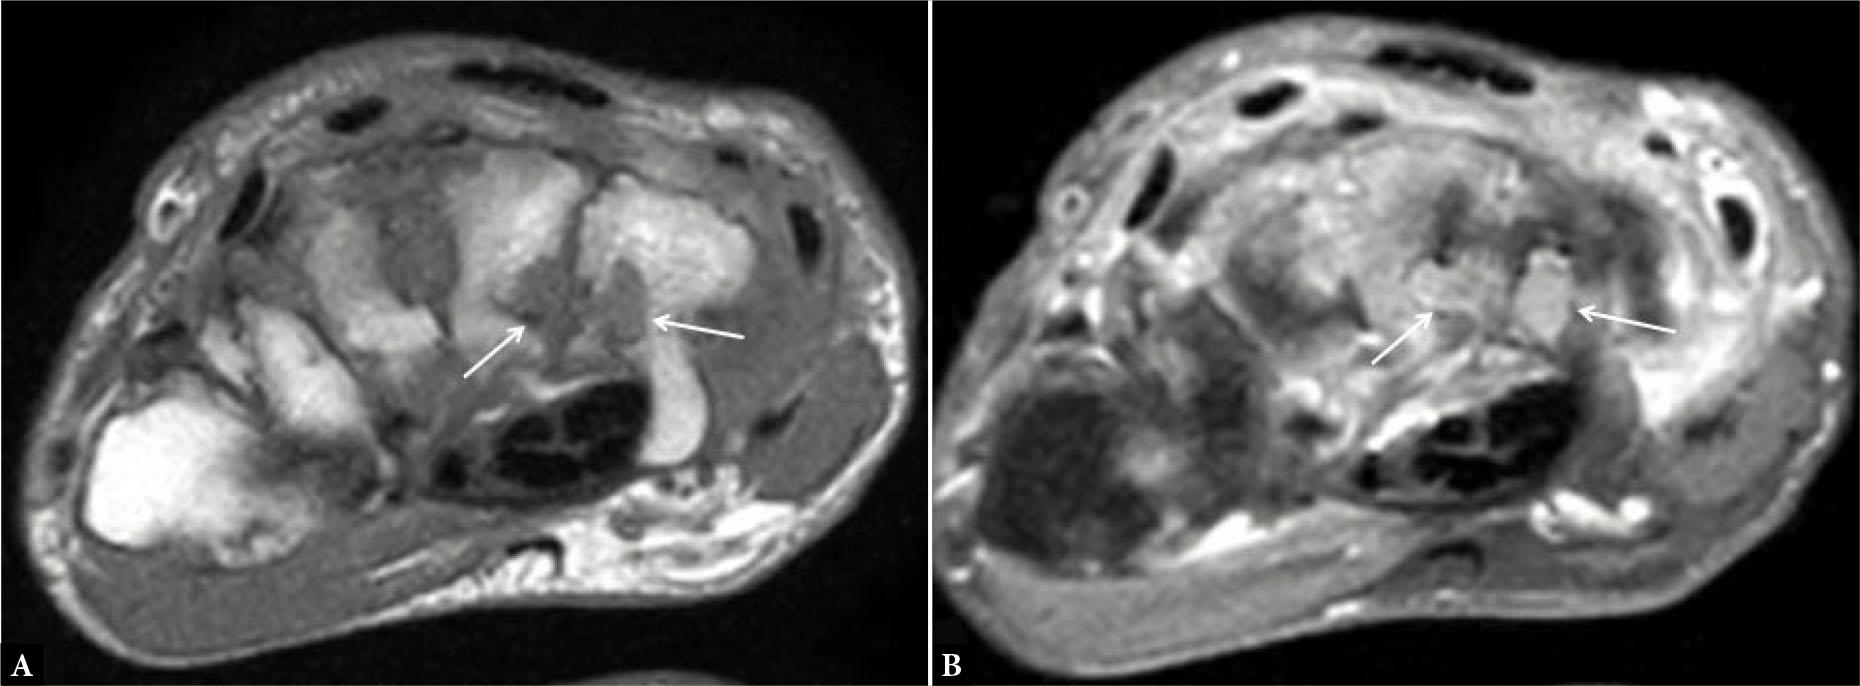

Fig. 6.

Axial post-contrast T1-weighted (T1W) fat-suppressed image of the distal radioulnar joint shows enhancing synovium (arrows in A), suggesting synovitis along with enhancement of the flexor and extensor tendon sheaths (arrows in B), consistent with tenosynovitis